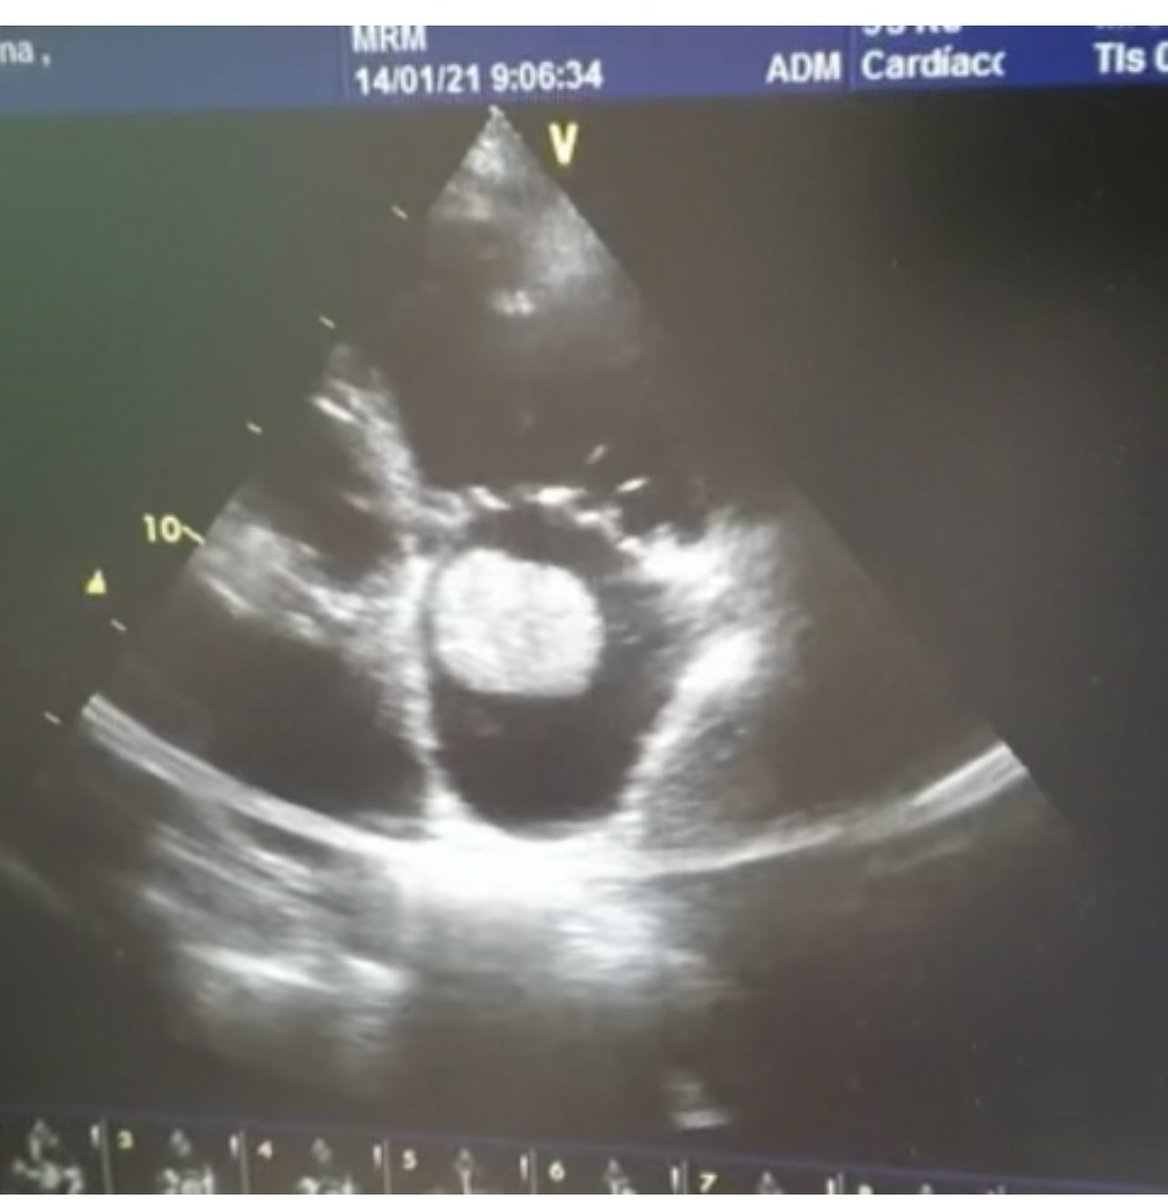

#POCUS quiz:

What's the jumping structure in the right ventricular outflow tract?

#FOAMed #MedEd #Nephpearls

Fracción de eyección aproximada 30%